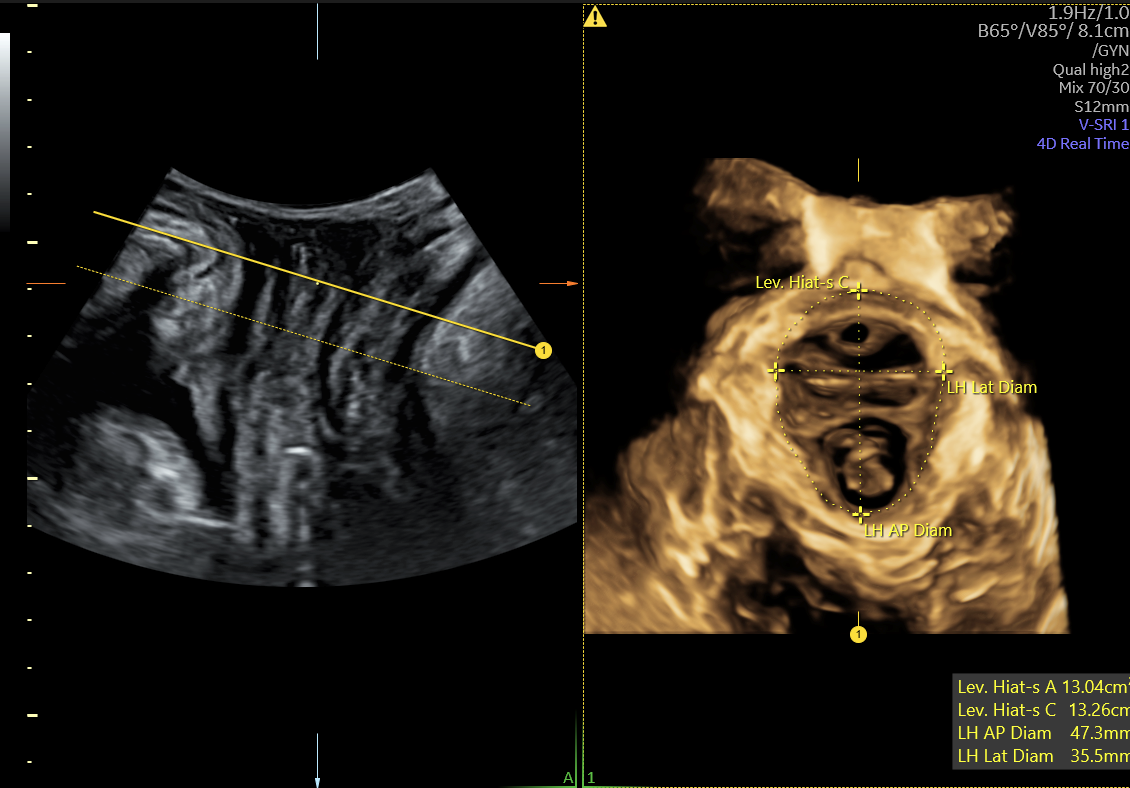

もう1つは、再現性のある骨盤底超音波画像の取得と計測をアシストする機能で、断面の位置合わせをリアルタイムに自動トラッキングして表示し、挙筋裂孔面積等の計測を装置がアシストします。(画像②)